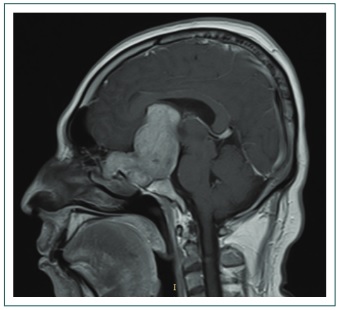

Varón de 43 años sin antecedentes que acude por cefalea y pérdida de visión periférica. Se realiza una resonancia magnética nuclear de hipófisis que informa un macroadenoma hipofisario de 62 × 54 × 52 mm (Fig. 1) que invade el tercer ventrículo y comprime el hipotálamo, por lo que se realiza adenectomía transesfenoidal parcial. Patología informa adenoma hipofisario de patrón sólido, predominantemente acidófilo, con la siguiente inmunohistoquímica: corticotropina (−), prolactina (−), hormona estimulante del folículo (+/+++), hormona luteinizante (−), hormona de crecimiento (−) y ki67 < 2%. Es dado de alta con prednisona 5 mg/día y levotiroxina 100 μg/día.

Resonancia magnética cerebral, corte sagital, en T1, que muestra un macroadenoma hipofisario.